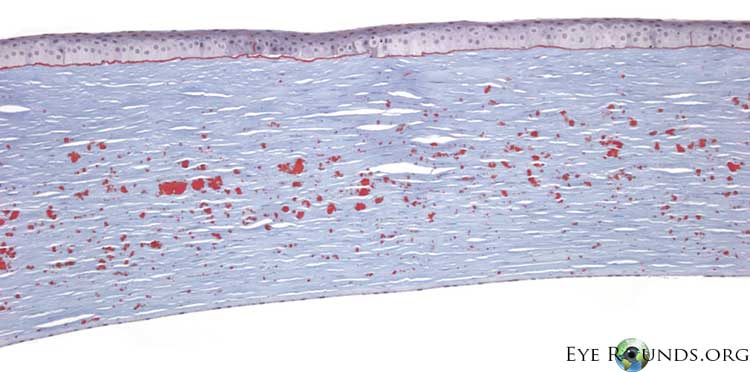

광학 현미경상,

과립성 호산성 침착물이 기질의 표층과 기질의 심부에 산재합니다.